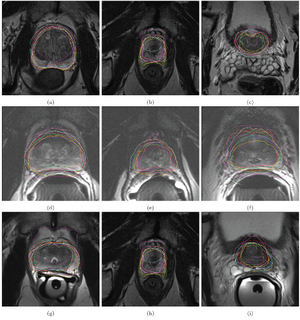

Publication: PLoS One. 2014 Oct 29;9(10):e110946. PMID: 25353989 | PDF Authors: Ho AL, Mouminah A, Du R. Institution: Department of Neurosurgery, Brigham and Women's Hospital, Harvard Medical School, Boston, MA, USA. Background/Purpose: Since the initial publication of the International Study of Unruptured Intracranial Aneurysms (ISUIA), management of unruptured intracranial aneurysms has been mainly based on the size of the aneurysm. The contribution of morphological characteristics to treatment decisions of unruptured aneurysms has not been well studied in a systematic and location specific manner. We present a large sample of basilar artery tip aneurysms (BTA) that were assessed using a diverse array of morphological variables to determine the parameters associated with ruptured aneurysms. Demographic and clinical risk factors of aneurysm rupture were obtained from chart review. CT angiograms (CTA) were evaluated with 3D Slicer, an open source visualization and image analysis software, to generate 3-D models of the aneurysms and surrounding vascular architecture. Morphological parameters examined in each model included aneurysm volume, aspect ratio, size ratio, aneurysm angle, basilar vessel angle, basilar flow angle, and vessel to vessel angles. Univariate and multivariate analyses were performed to determine statistical significance. From 2008-2013, 54 patients with BTA aneurysms were evaluated in a single institution, and CTAs from 33 patients (15 ruptured, 18 unruptured) were available and analyzed. Aneurysms that underwent reoperation, that were associated with arteriovenous malformations, or that lacked preoperative CTA were excluded. Multivariate logistic regression revealed that a larger angle between the posterior cerebral arteries (P1-P1 angle, p = 0.037) was most strongly associated with aneurysm rupture after adjusting for other morphological variables. In this location specific study of BTA aneurysms, the larger the angle formed between posterior cerebral arteries was found to be a new morphological parameter significantly associated with ruptured BTA aneurysms. This is a physically intuitive parameter that can be measured easily and readily applied in the clinical setting.

Figure 2 3D model of BTA aneurysm depicting angular variables of the surrounding vasculature. There were three vessel to vessel angles -measured. The Parent-Daughter angle is a composite angle that refers to the average of the two angles formed between the basilar artery (BA) and each posterior cerebral artery (RPCA, LPCA). The P1-P1 angle refers to the angle formed between the two posterior cerebral arteries (RPCA, LPCA). The SCA-SCA angle refers to the angle formed between the two superior cerebellar arteries (RSCA, LSCA). This 3D surface model of the aneurysm and surrounding vessels could be manipulated freely in the 3D Slicer environment. Volumes, lengths, and angles were then manually measured with fiducial-based tractography. |